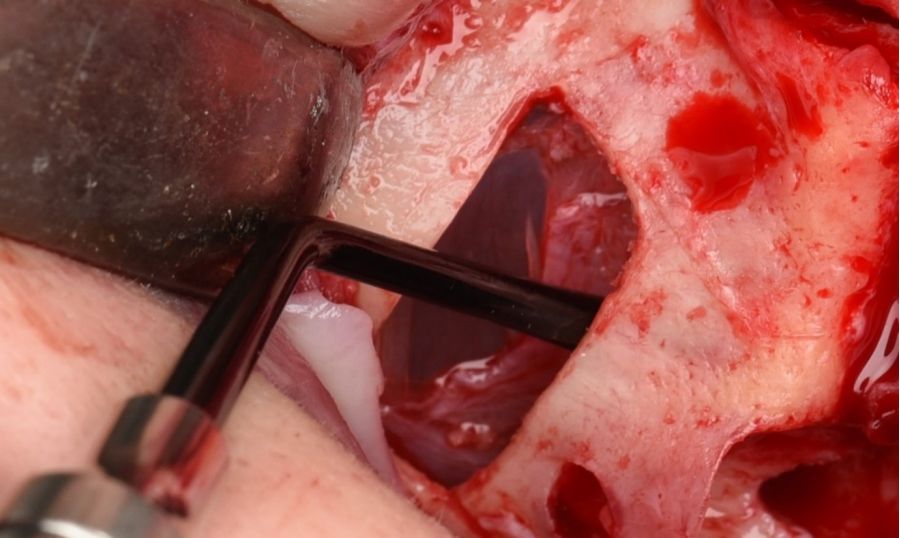

La ostectomía de acceso al seno maxilar en la pared anterior y lateral del seno maxilar de 2.5×0,8 cm se realizó con bisturí piezoeléctrico con inserto de osteotomía de diamante no dentado y abundante irrigación con suero salino (Figura 6). A continuación, se despegó la cortical y se sumergió en suero fisiológico hasta el final de la intervención (Figura 7). Se procedió a incidir la mucosa de Schneider en la zona más superior de la ventana, de mesial a distal en toda la anchura de la ostectomía, hasta penetrar en la luz del pseudoquiste (Figuras 8 y 9). Se realizó el aspirado del contenido del pseudoquiste y el epitelio del pseudoquiste se retiró cuidadosamente con una cucharilla de legrado y curetas de elevación (Figuras 10 y 11). Posteriormente, se desinfectó la cavidad con povidona yodada e irrigación con abundante suero salino. Una vez eliminado el pseudoquiste se procedió al despegamiento de la membrana de Schneider según la técnica habitual de elevación de seno maxilar abierta (Figura 12). Tras comprobar un correcto despegamiento de la membrana de Schneider se realizaron dos perforaciones con bisturí piezoeléctrico e inserto de bola de 3 mm craneales al límite superior de la ostectomía inicial (Figura 13). Se suturó la mucosa de Schneider a estas perforaciones mediante puntos simples con sutura reabsorbible 4/0 (Novosyn quick®) (Figura 14). Se colocó en el interior de la cavidad, en la zona superior, una membrana reabsorbible de colágeno (Geitlisch Bio-Guide®) que se dejó sobresalir de la cavidad hacia el exterior 1 cm (Figura 15). Se procedió al relleno de la cavidad con xenoinjerto (Geitlisch Bio-Oss® de gránulo grueso 1-2 mm) (Figura 16). La tapa de cortical que se había extraído tras la ostectomía se reposicionó y se cubrió con la membrana de colágeno que se había dejado expuesta en la zona superior (Figuras 17 y 18). Finalmente, se reposicionó el colgajo y se suturó con sutura de nylon 5/0 monofilamento no absorbible (Figura 19).